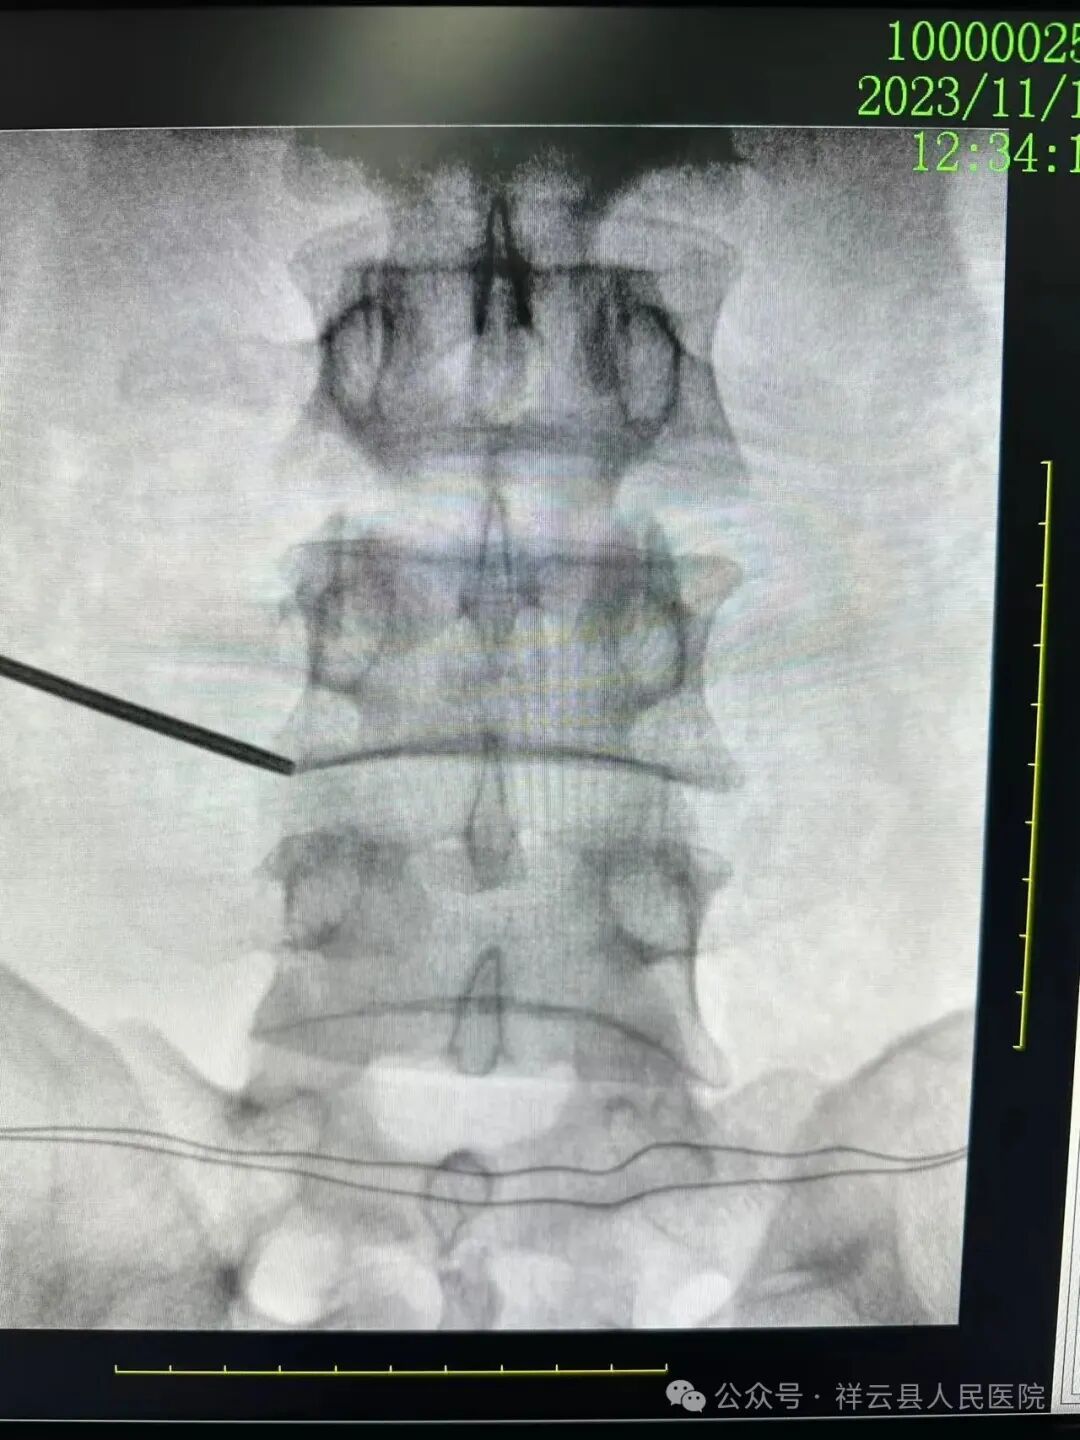

以脊柱相关疾病的诊断、治疗和研究为目的,结合患者症状、体征及影像学资料,开展颈肩、腰腿痛MDT,为患者提供个性化的诊断及治疗方案,综合应用药物治疗、神经阻滞、物理治疗等手段,实施精准诊疗;采用现代脊柱微创治疗理念,充分运用脊柱内镜技术,开展各类脊柱微创手术:如椎间孔镜下颈椎、腰椎间盘摘除,椎板切除椎管扩大减压等手术;不断探索、优化,在关节镜辅助下,运用UBE、AUSS等脊柱内镜技术,治疗颈、胸、腰椎管狭窄症,颈椎、腰椎间盘突出症及腰椎滑脱症等疾病,减少对周围组织的损伤,缩短恢复时间,提升患者就医感受。在脊柱微创治疗理念的引导下,常规实施颈椎前路、腰椎后路小切口或肌间隙入路下脊柱固定和融合手术,使用颈椎前后路钢板、颈腰椎后路钉棒系统、椎间融合器等器械,恢复脊柱结构的稳定性,改善脊柱的生物力学和外观,减轻神经压迫,恢复患者的活动能力,减少术后复发概率。